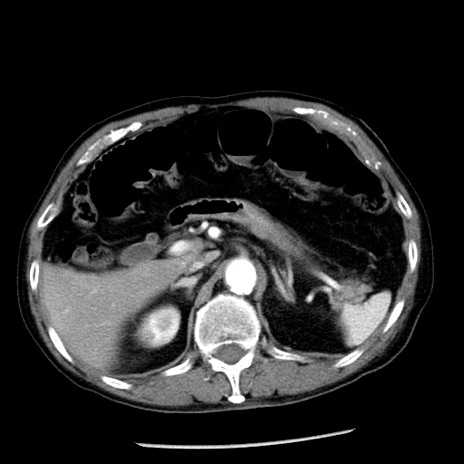

症例26(横断像)

【症例】80歳代男性

【主訴】嘔吐

【現病歴】昨晩2回嘔吐あり、今朝になっても嘔吐あり。来院。

【既往歴】胃潰瘍

【身体所見】意識清明、BT 37.6℃、BP 166/95mmHg、HR 100bpm、SpO2 97%、腹部:平坦・軟、腸蠕動音聴取良好、圧痛なし。

【データ】WBC 21900、CRP 1.46